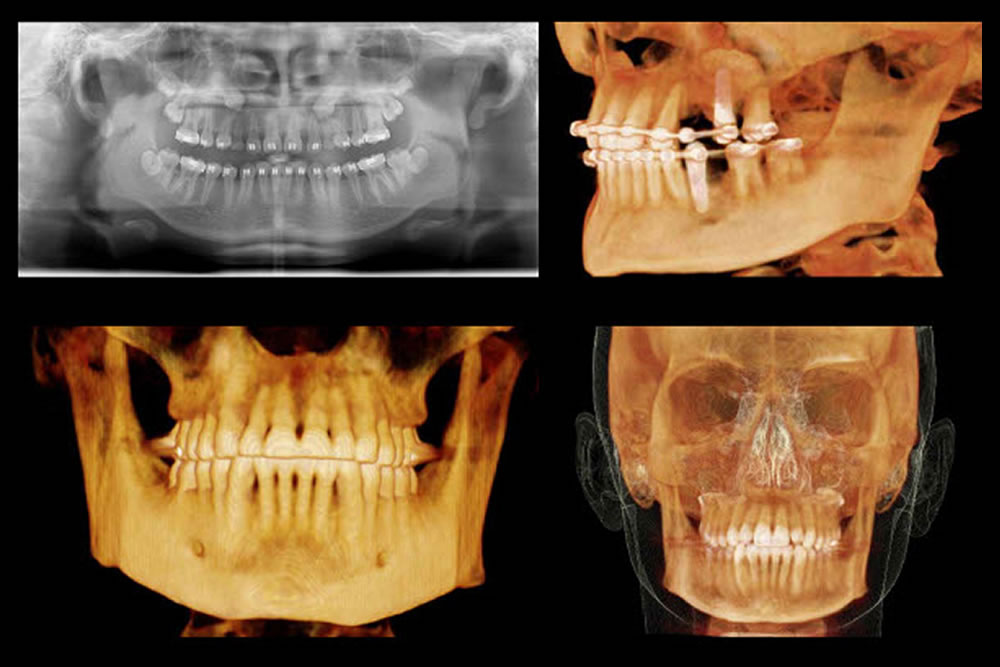

CTを駆使した精密検査

親知らずが歯茎に埋まったままの場合や歯根が大きく湾曲している場合など、難抜歯の可能性が高い場合には、必要に応じてCTによる精密検査を実施いたします。親知らずの状態はもちろん、周囲の神経や血管の位置をきちんと把握し、適切な抜歯計画を立案いたします。